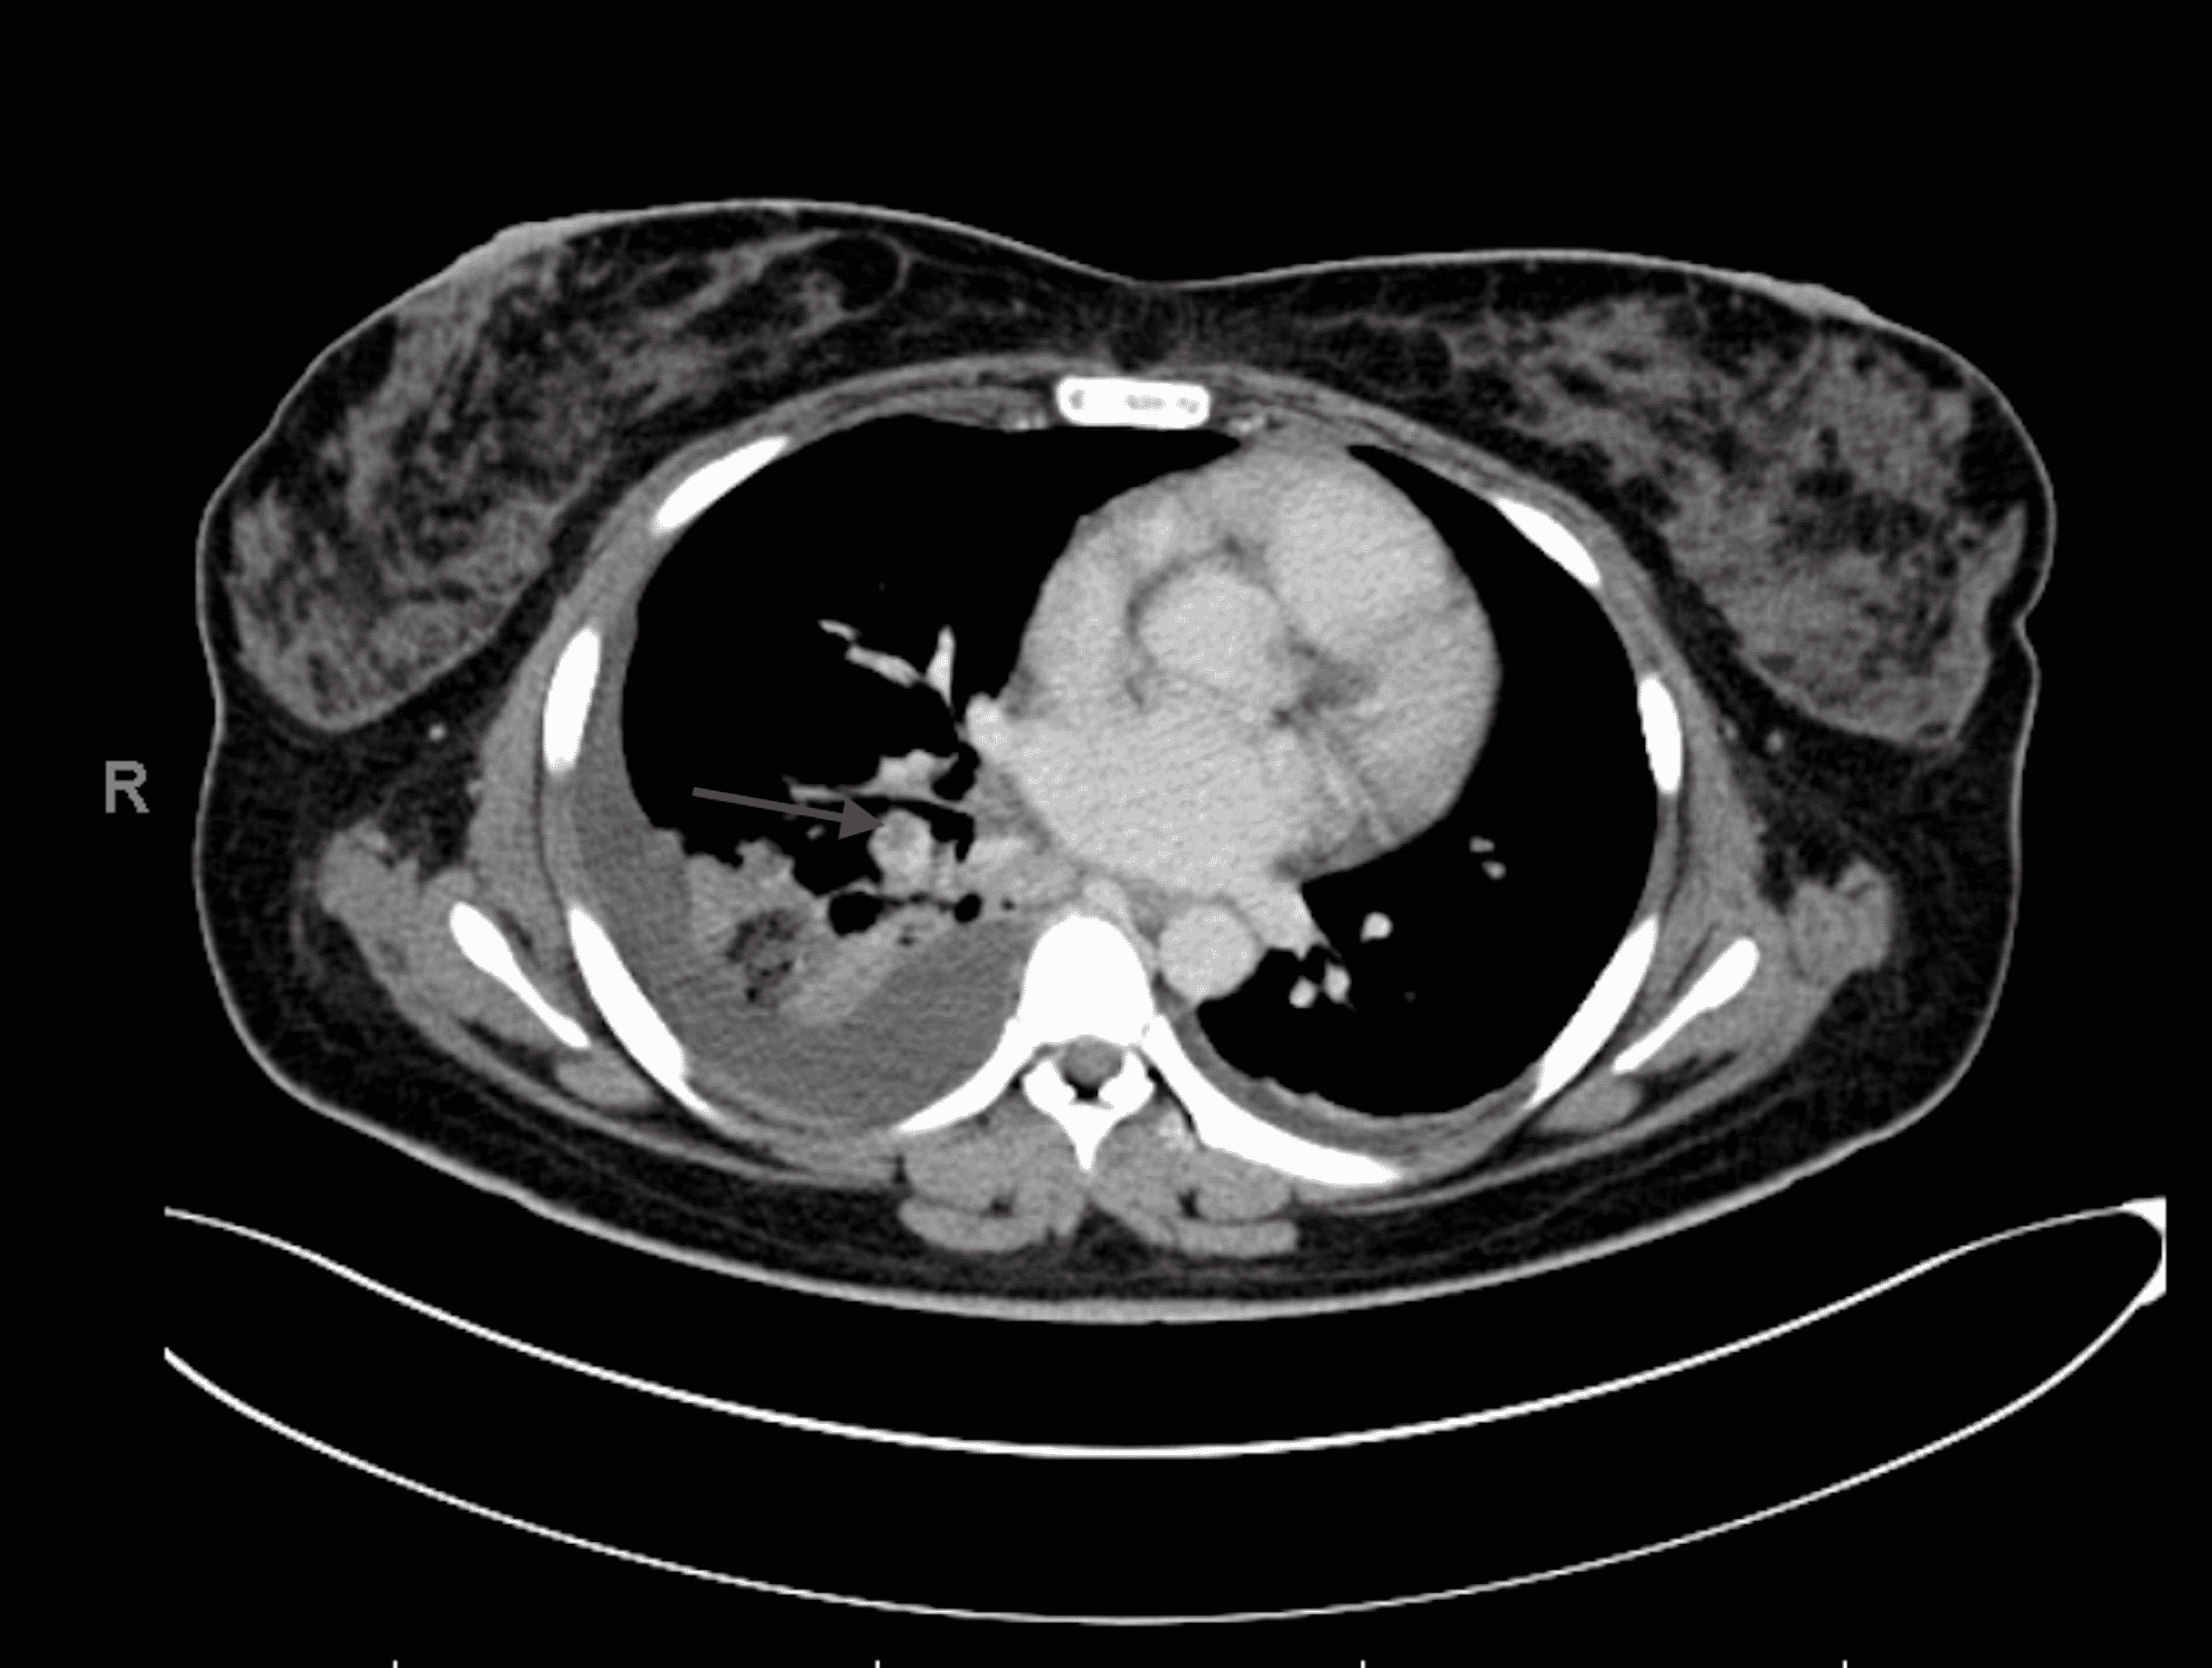

From www.researchgate.net

Acute pulmonary embolism on axial iodine (perfusion) map CT image in a Chest Pain Left Side Pulmonary Embolism If you have these symptoms, get. There are several treatments for a pulmonary embolism. It may have no symptoms and. A pulmonary embolism (pe) can cause symptoms such as chest pain or breathlessness. The pain is often sharp and felt when you breathe in deeply. If you have symptoms like chest pain, coughing up blood or trouble breathing get medical. Chest Pain Left Side Pulmonary Embolism.